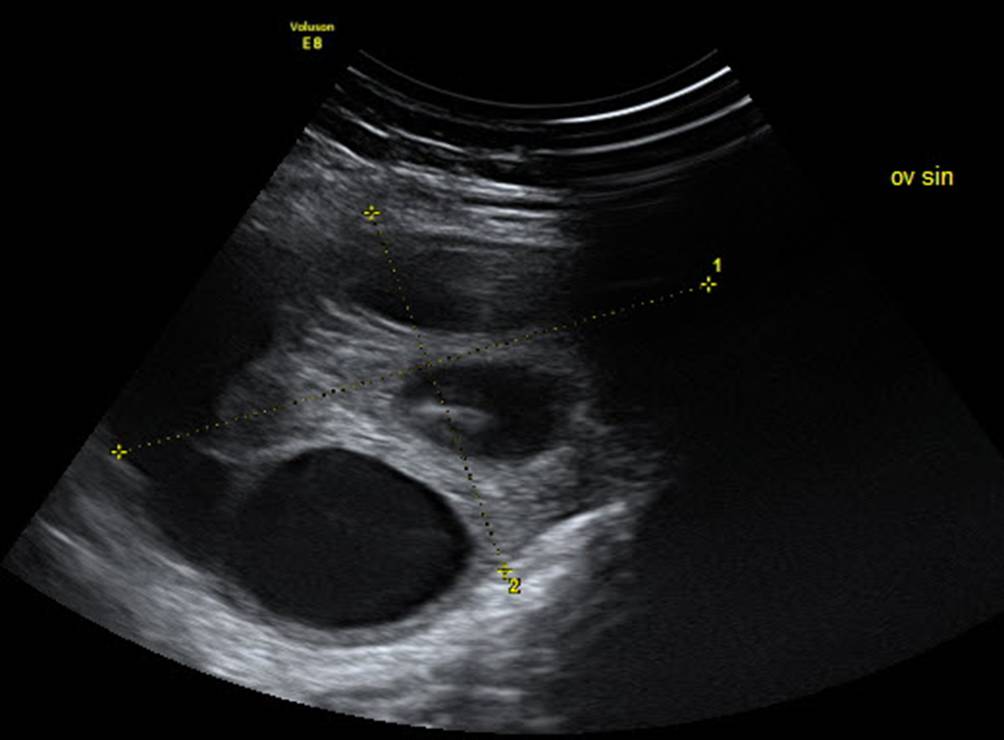

Abb. 12

Normales Ovar einer 13-jährigen Patientin, die mit Verdacht auf PCO zugewiesen wurde, im Abdominalschall